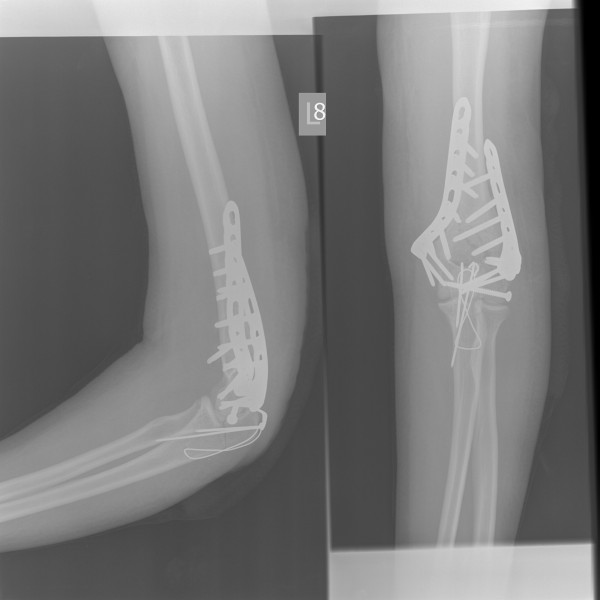

Ta kość, która jest prostopadła, powinna być równoległa, tak. W wyniku wielu dziwnych przygód z naszą ukochaną, polską służbą zdrowia, już tydzień później wyglądało to tak.

A kolejny tydzień później przyjęło wygląd mniej-więcej obowiązujący do teraz: